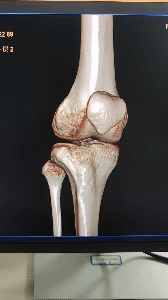

3D重建,立体呈现

飞利浦Incisive AI CT还具备3D重建成像技术,能够将复杂的解剖结构以三维的形式呈现出来,为医生提供更为直观的视觉辅助,从而帮助医生更好地理解和解释病变情况,提升诊断准确性。

Incisive CT的O-MAR技术能消除金属伪影,能清晰显示移植物的位置及临近组织结构。

▲ 骨折术后、内固定器材清晰显示